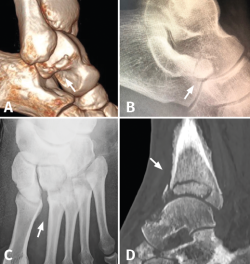

Figura 2. A: fractura pars lateral del astrágalo (snowboarder’s fracture); B: fractura pars anterior del calcáneo; C: lesión sutil de Lisfranc; D: neuroartropatía diabética de Charcot de la tibia distal.

El tiempo medio de demora hasta el diagnóstico fue de 38,5 días (rango: 2-270 días). En 14 casos (56%) el diagnóstico definitivo se realizó en urgencias tras requerir el paciente una nueva valoración, al considerar que la evolución no estaba siendo la adecuada. La prueba complementaria que permitió la detección de la lesión fue en 6 casos (24%) la misma radiografía realizada previamente, en la cual se podía visualizar la lesión; una nueva radiografía diferente a la inicial en 6 casos (24%); la TC en 10 casos (40%); y una RM en 3 casos (12%) (Figura 2).